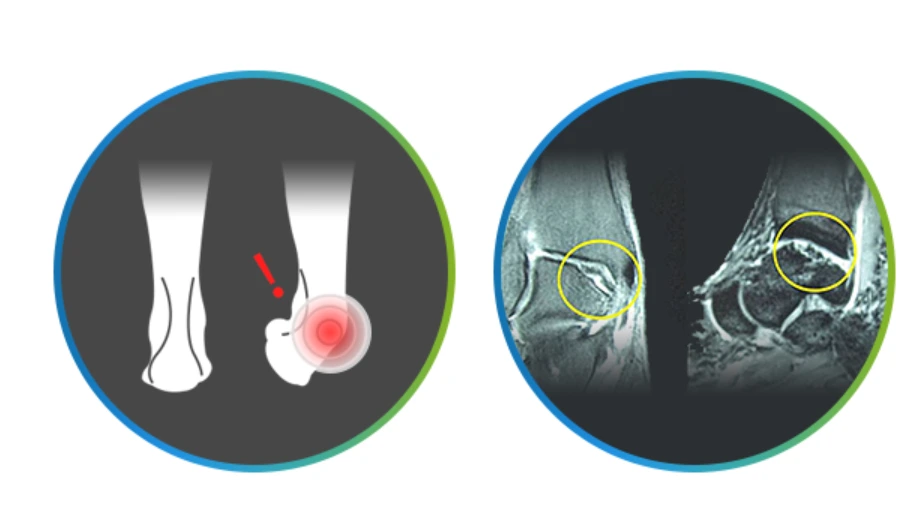

발목연골손상.PNG

발목염좌와 같은 외상을 그냥 두었다가 발목연골손상으로 발전하는 경우가 많은데요. 발목관절의 부종, 통증, 잠김 현상 등이 나타나며 갑자기 발목에 심한 통증이 나타났다가 자연적으로 좋아지는 증상이 반복되는 것이 특징입니다. 발목 손상 이후에 지속적인 통증과 불편함이 있고, 발목에서 소리가 나거나 관절에서 걸리는 느낌이 있기도 하며, 발목 관절의 부종이 지속되고 움직이는 정도가 이전보다 줄어들면 발목연골손상을 의심해야 해요.

더군다나 발목연골손상을 발목염좌처럼 그냥 방치했다가는 관절염으로 진행되니 주의해야 해요.

발목관절염

“발목에 무슨 관절염이요”이란 말을 하는 분들이 있으신 데요. 발목관절염은 퇴행성변화가 주원인인 무릎관절염과 달리 발목염좌와 같은 외상이 주원인입니다. 발목염좌로 인한 인대손상을 방치한다면 비교적 젊은 나이에도 발목관절염이 발생할 수 있어요.

캡처.PNG

발목관절염 증상으로는 극심한 통증과 붓기가 있습니다. 그러나 가장 무서운 것은 발목관절염이 진행되면서 발목의 모양이 점점 변형된다는 것이랍니다.